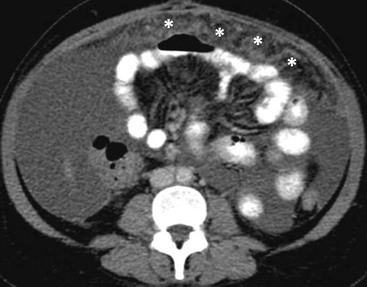

MDCT with coronal and sagittal reformations (Fig. 30-19) is considered the optimal technique for detecting the presence, location and extent of peritoneal carcinomatosis; overall diagnostic accuracy of 94%, specificity of 92% and sensitivities between 75 and 81% have been reported;22 however, sensitivity for identifying small lesions by MDCT is significantly lower. Implantation of tumour deposits along the peritoneal surfaces of the diaphragm, liver and spleen results in smooth, nodular, or plaque-like thickening and contrast enhancement of the parietal peritoneal lining. However, these features are not specific for peritoneal carcinomatosis as they may be seen with other processes that seed the peritoneum, including tuberculosis, peritoneal mesothelioma and peritoneal lymphomatosis. Contrast-enhanced T1-weighted MR images with fat saturation can improve the detection of smaller or equivocal implants or of numerous very small implants that may be manifested as a contiguous ‘line-type’ enhancement along the peritoneal surfaces (Fig. 30-20). Peritoneal tumours often enhance slowly and are best seen on images obtained 5 min after injection of gadolinium. The combination of diffuse-weighted images (DWI) and conventional MRI improves the accuracy of MRI for depicting peritoneal implants;23 therefore, DWI is suggested as an indispensable part of any MRI evaluation in patients suspected for PC.23 DW-MRI and FDG-PET/CT are promising methods for the evaluation of peritoneal carcinomatosis,23,24 but still have a limited role, especially for the identification of disease relapse after treatment. Calcification within peritoneal implants before chemotherapy suggests that the primary site is either serous papillary cystadenocarcinoma of the ovary, or, rarely, gastric carcinoma (Fig. 30-21).